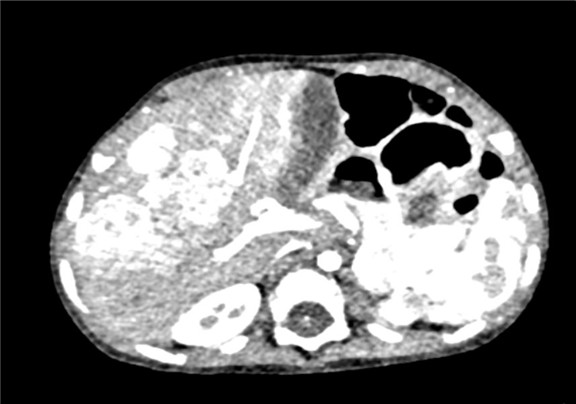

上腹部增强CT:肝脏占位性病变,疑似肝母细胞瘤,或血管母细胞瘤.

术前CT检查:

动脉期

静脉期